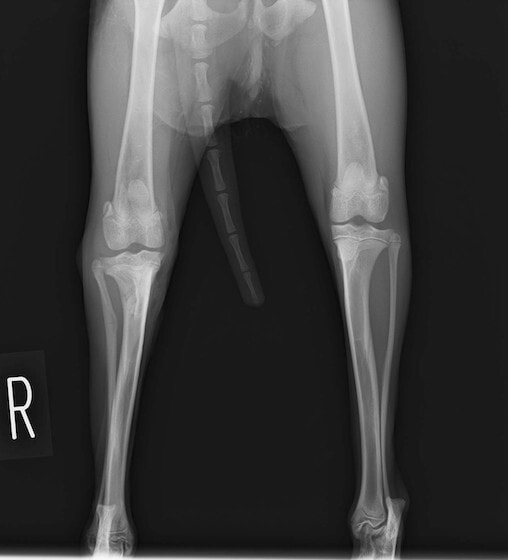

症例3:キルシュナーワイヤーのピンニングによる整復

ペルシャ猫 11ヶ月齢 雄

他院にて左大腿骨遠位の成長板骨折(salter-harrisⅠ型)が認められており、治療相談を目的として来院。当院にて、キルシュナーワイヤーを用いたピンニングにより骨折部位の整復を行いました。術後の経過は良好で、現在も経過観察中です。

術前レントゲン

術後レントゲン